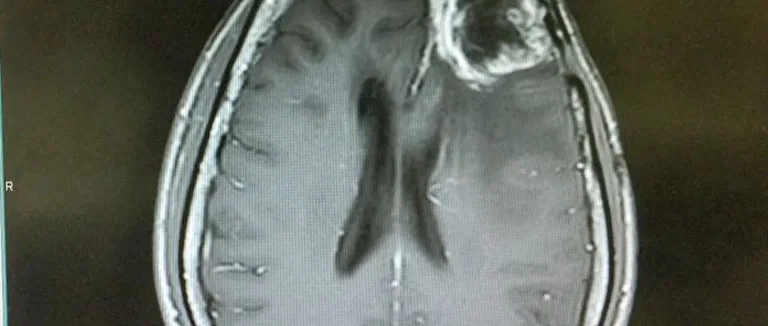

L'imagerie par résonance magnétique (IRM) a changé le diagnostic des tumeurs cérébrales. La qualité et la précision des images IRM s'améliorent sans cesse. Cela aide à créer des systèmes de diagnostic automatisés et des algorithmes d'apprentissage automatique.

L'IRM cérébrale utilise des champs magnétiques et des ondes radio pour créer des images détaillées. Cette technique permet de voir les structures du cerveau avec précision. Cela aide à diagnostiquer les tumeurs cérébrales.

Les images IRM montrent bien la taille, la forme et la localisation des tumeurs. Ces détails sont cruciaux pour choisir le bon traitement.